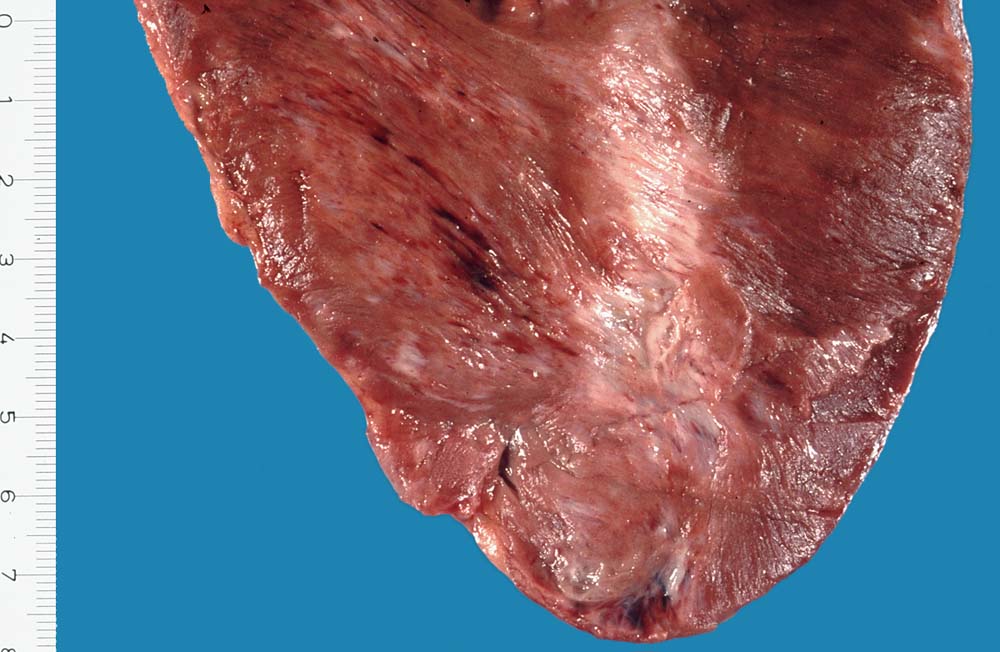

Morphologie:

Eine restitutio ad integrum nach abgelaufener Myokardnekrose ist nicht möglich. Wird das Ischämieereignis überlebt, kommt es zu einer reparativen Regeneration mit Ersatz der Muskulatur durch kollagenreiches Narbengewebe. Dieser Vorgang setzt etwa ab dem 9. Tag nach Infarkt ein und dauert bis zur vollständigen narbigen Ausheilung bei transmuralem Infarkt etwa 50 Tage. Makroskopisch imponiert die Narbe als fasriges weisses derbes Areal. Von einem Infarkt spricht man, wenn die Nekroseareale einen Durchmesser von mindestens 3cm Durchmesser haben. Ab dieser Grösse kann klinisch das Bild eines Myokardinfarktes ausgelöst werden. Kleinere, makroskopisch sichtbare Narben werden als grobfleckige Myokardfibrose (> 873) (> 234) bezeichnet.